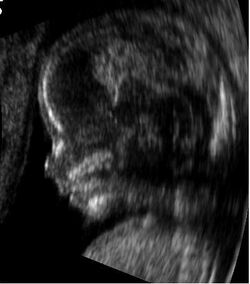

Modern 3D ultrasound images provide greater detail for prenatal diagnosis than the older 2D ultrasound technology.[6] While 3D is popular with parents desiring a prenatal photograph as a keepsake,[7] both 2D and 3D are discouraged by the FDA for non-medical use,[8] but there are no definitive studies linking ultrasound to any adverse medical effects.[9] The following 3D ultrasound images were taken at different stages of pregnancy:

Fetus at 17 weeks